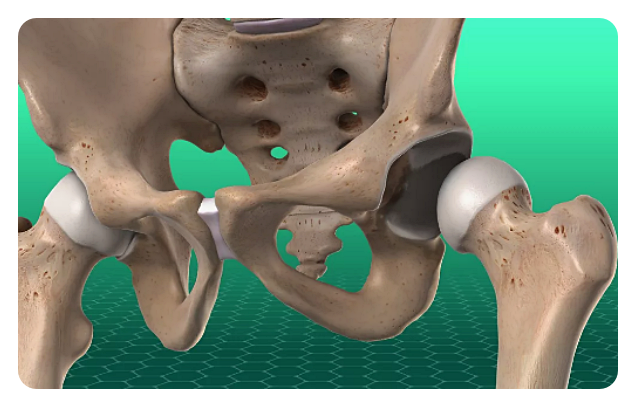

고관절은 몸을 지탱하고 움직이는 데 중요한 역할을 하는데, 골반과 대퇴골을 연결하는 관절입니다. 우리의 일상적인 활동에서도 이 관절은 걷기나 뛰기와 같은 움직임뿐만 아니라 체중을 지탱하고 다리를 움직이는 데에 필수적입니다. 그러나 나이가 들거나 부상 등으로 고관절이 손상되면 통증과 움직임 제한과 같은 문제가 발생할 수 있습니다.

인공관절 치환술: 이 수술은 고관절이 심각하게 손상되거나 통증으로 인해 일상 생활에 지장을 주는 경우에 시행됩니다. 이 수술은 손상된 관절을 제거하고 인공 관절로 대체함으로써 이루어집니다.

고관절 인공관절 수술은 손상된 부위를 대체하고 통증을 완화하는 데에 효과적입니다. 또한 환자의 개인적인 상황에 맞춰 맞춤형 수술이 가능하며, 통증 완화와 관절 기능 개선을 통해 삶의 질을 향상시킵니다. 이러한 수술은 장기적인 효과를 가지며, 환자들에게 삶의 활동성을 되찾을 수 있는 기회를 제공합니다.